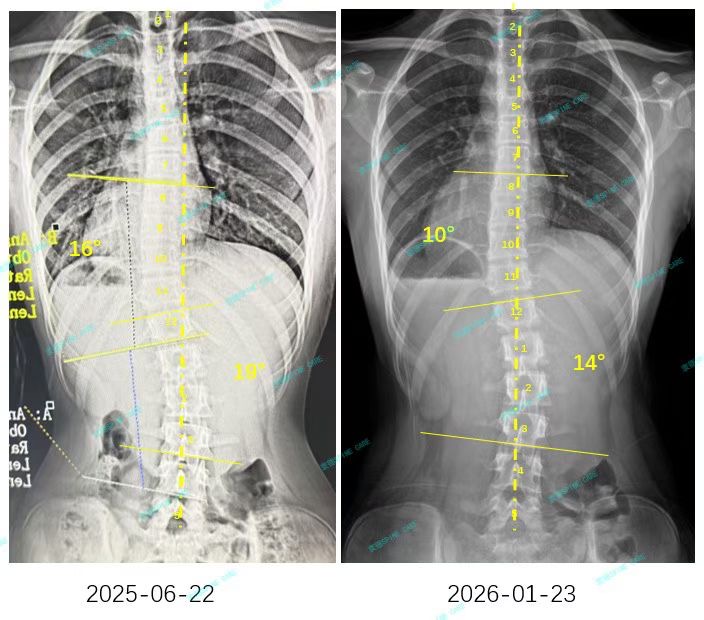

来自家长对衷德的评价(小逸妈妈)